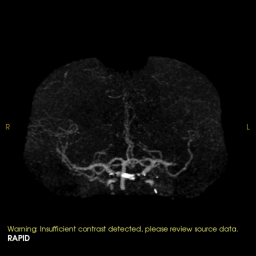

3. Mechanical Thrombectomy with aspiration only technique

Mechanical Thrombectomy with aspiration only technique CT, CT perfusion and angiogram images

Young patient with left sided dense hemiplegia while working out in gym. Time of onset 3 hrs. Plain CT demonstrates early changes of acute stroke in the right MCA territory (A). CTA confirms right M1 occlusion (B). Perfusion imaging (C) shows mismatch ratio of 7.9 with good volume of salvageable brain (green shade). DSA re-demonstrated the right M1 occlusion which was successfully removed using only suction, ADAPT resulting in TICI 3 outcome (E).